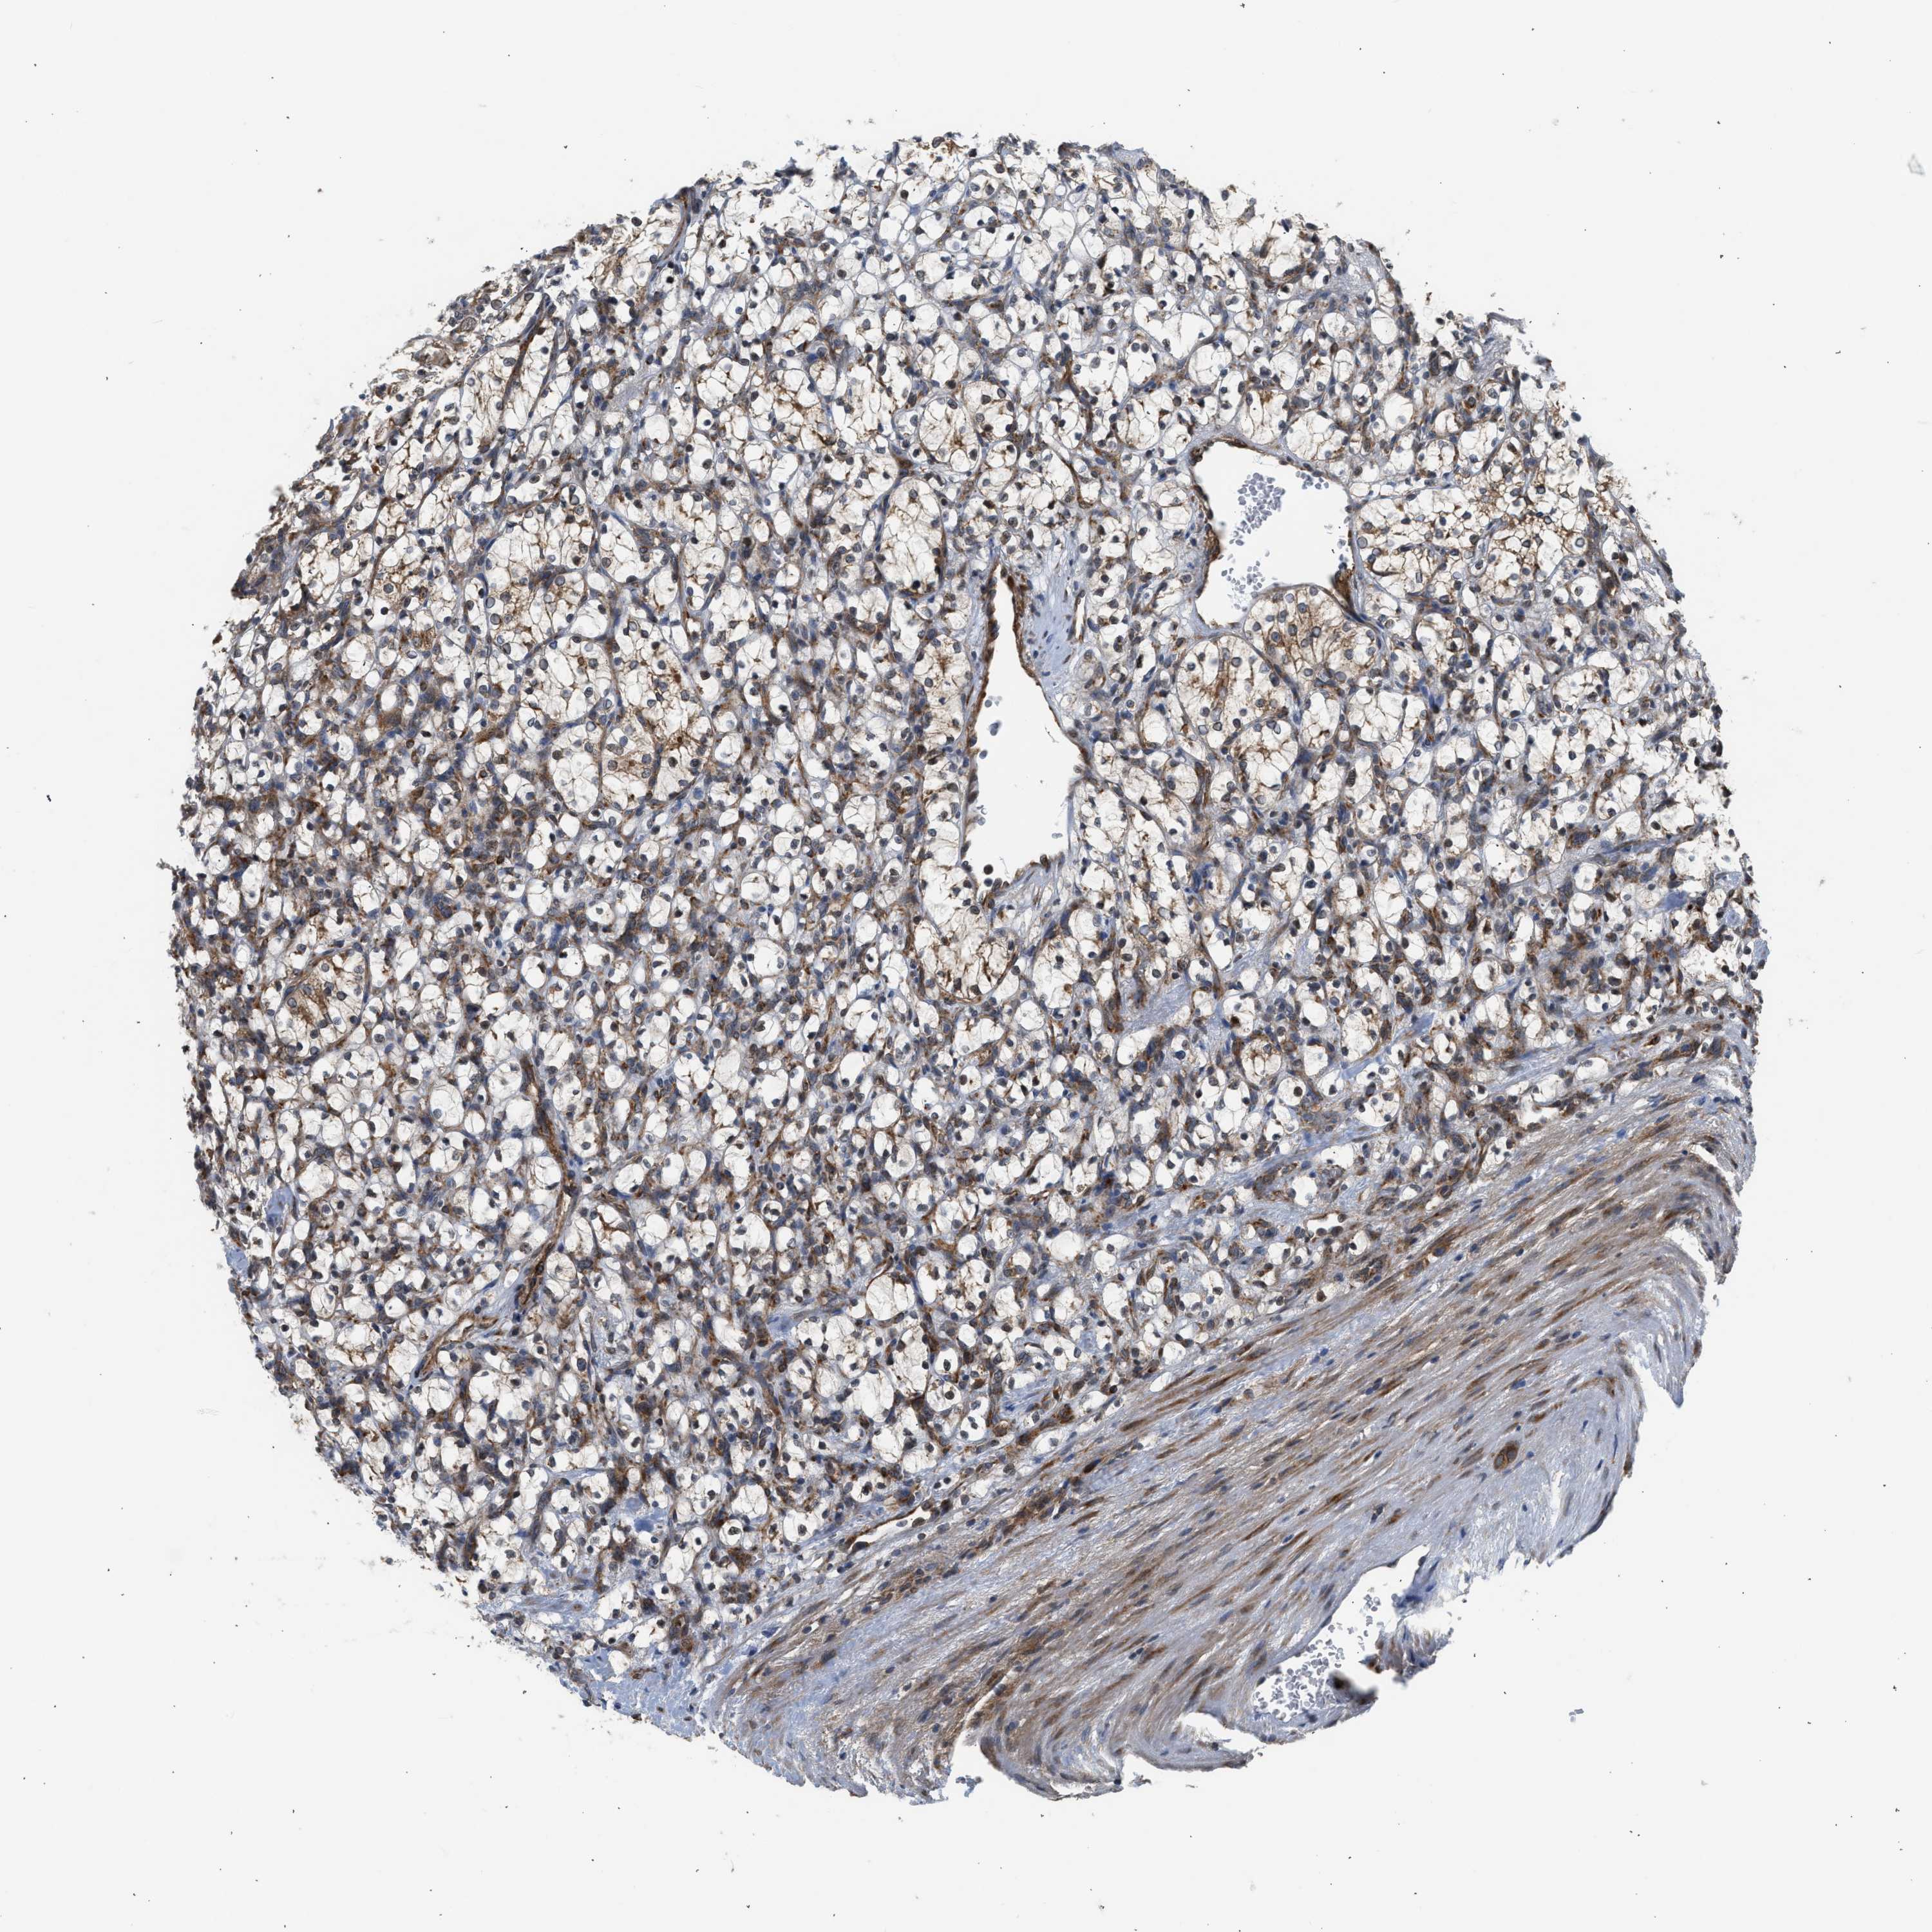

KIDNEY RENAL CLEAR CELL CARCINOMA (VALIDATION) - Interactive survival scatter ploti

The Survival Scatter plot shows the clinical status (i.e. dead or alive) for all individuals in the patient cohort, based on the same data that underlies the corresponding Kaplan-Meier plots. Patients that are alive at last time for follow-up are shown in blue and patients who have died during the study are shown in red.

The x-axis shows the expression levels (FPKM) of the investigated gene in the tumor tissue at the time of diagnosis. The y-axis shows the follow-up time after diagnosis (years). Both axes are complimented with kernel density curves demonstrating the data density over the axes. The top density plot shows the expression levels (FPKM) distribution among dead (red) and alive patients (blue). The right density plot shows the data density of the survived years of dead patients with high and low expression levels respectively, stratified using the cutoff indicated by the vertical dashed line through the Survival Scatter plot. This cutoff is automatically defined based on the FPKM cutoff that minimizes the p-score. The cutoff can be changed by dragging the vertical line or by entering a cutoff value in the square labeled "Current cut-off".

Under the Survival Scatter plot the p-score landscape (black curve; left axis) is shown together with dead median separation (red curve; right axis). Dead median separation is the difference in median mRNA expression between patients who have died with high and low expression, respectively. It is calculated as follows: median FPKM expression of dead patients with high expression - median FPKM expression of dead patients with low expression. This is intended to aid the user in visually exploring custom cutoffs and the associated p-scores and dead median separation.

Individual patient data is displayed and can be filtered by clicking on one or more of the category buttons on the top of the page. Categories describing expression level and patient information include: high, low, alive, dead, female, male and tumor stages. The scale of the x-axis can be toggled between linear and log-scale by clicking on the "x log" button. Mouse-over function shows TCGA ID, patient information and mRNA expression (FPKM) for each patient.

& Survival analysisi

Kaplan-Meier plots summarize results from analysis of correlation between mRNA expression level and patient survival. Patients were divided based on level of expression into one of the two groups "low" (under cut off) or "high" (over cut off). X-axis shows time for survival (years) and y-axis shows the probability of survival, where 1.0 corresponds to 100 percent.

POLG2 is not prognostic in Kidney Renal Clear Cell Carcinoma (validation)

Best expression cut offi

Based on the FPKM value of each gene, patients were classified into two groups and association between prognosis (survival) and gene expression (FPKM) was examined. The best expression cut-off refers the FPKM value that yields maximal difference with regard to survival between the two groups at the lowest log-rank P-value. Best expression cut-off was selected based on survival analysis .

When clicking on this number, the vertical dashed line indicating cut-off, the interactive survival plot, and the Kaplan-Meier curve will be adjusted to show results based on the best expression cut-off.

: 4.51

P scorei

Log-rank P value for Kaplan-Meier plot showing results from analysis of correlation between mRNA expression level and patient survival.

N/A

TCGA RNA samplesi

RNA-seq data is reported as average FPKM (number Fragments Per Kilobase of exon per Million reads), generated by the The Cancer Genome Atlas (TCGA) .

Normal distribution across the dataset is visualized with box plots, shown as median and 25th and 75th percentiles. Points are displayed as outliers if they are above or below 1.5 times the interquartile range. FPKM values of the individual samples are presented next to the box plot.

Average pTPM 6.1

Number of samples 100